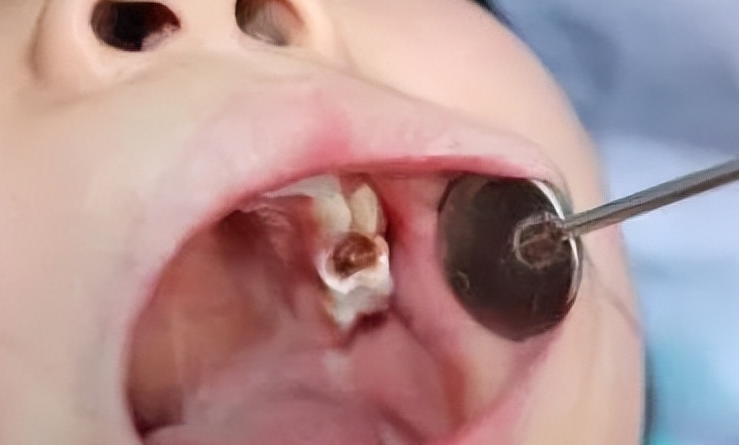

齲齒是一種非常常見的口腔疾病,在臨床上有發(fā)病率高,發(fā)病的人群廣,危害多等等情況。當(dāng)牙友們?nèi)绻旋x齒的話,就需要及時做修復(fù)處理,畢竟如果不及時修復(fù)處理的話,慢慢的就會脫落壞掉得不償失,影響更為巨大。齲齒治療疼不疼?這或許是牙友們比較在意的事情,接下來,我們一起來了解一下。

齲齒治療是否疼痛,需要看齲齒的惡化程度。如果僅僅是淺齲或者中齲,這時候患者是沒有任何疼痛反應(yīng)的。如果是深齲,就有可能存在強烈的疼痛反應(yīng),這時候務(wù)必要在術(shù)前進行局部麻醉,否則手術(shù)很難完成。齲齒是一種會不斷惡化發(fā)展的疾病,這種疾病早期癥狀不明顯,發(fā)展到中齲時,齲洞才會出現(xiàn),這時候就務(wù)必及時醫(yī)院就診,否則還會進一步惡化。

齲齒在做治療的時候疼還是不疼,也要看齲齒到底有什么樣的癥狀,齲齒到底有多深。如果只是比較淺的齲齒,那么只要做補牙治療,做補牙治療是沒有疼痛的。如果齲齒比較深,已經(jīng)有冷熱酸甜刺激疼痛,那么在去齲壞組織的時候,有可能出現(xiàn)明顯的敏感癥狀,出現(xiàn)敏感疼痛。